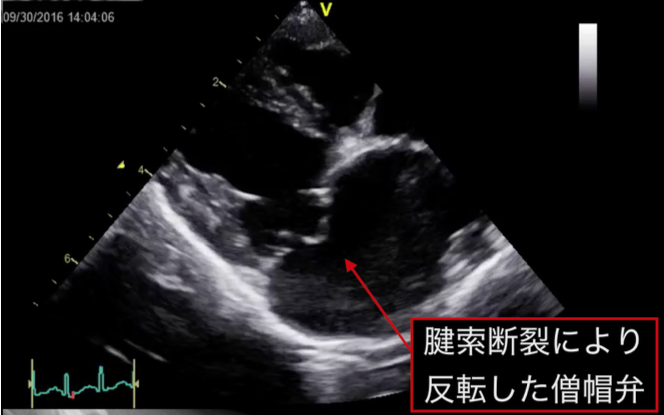

しかし僧帽弁の閉鎖がうまくいかない一つの原因としては、僧帽弁の腱索というパラシュートのヒモのような部分が、断裂し僧帽弁が支えられない状態となっている事が多いと言われています。

その場合には、人工心肺を使用し心臓を一度停止させ、心臓の内部を修復する手術による治療が 効果的です。僧帽弁を修復すると弁の接合は非常に綺麗な状態となり、投薬も不要となることが 多いです。拡大した心臓は手術後小型化し、状態にもよりますがこの症例は正常なワンちゃんと 同等の心臓サイズまで戻りました。